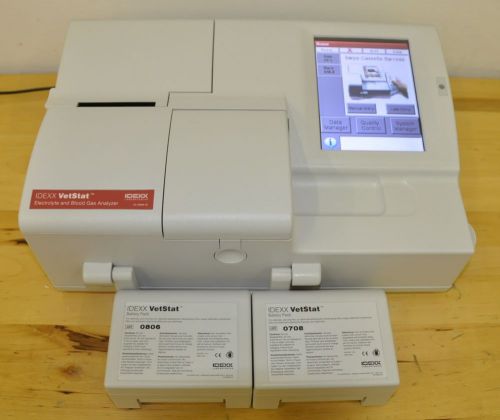

IDEXX VETSTAT ELECTROLYTE AND BLOOD GAS ANALYZER VETERINARY